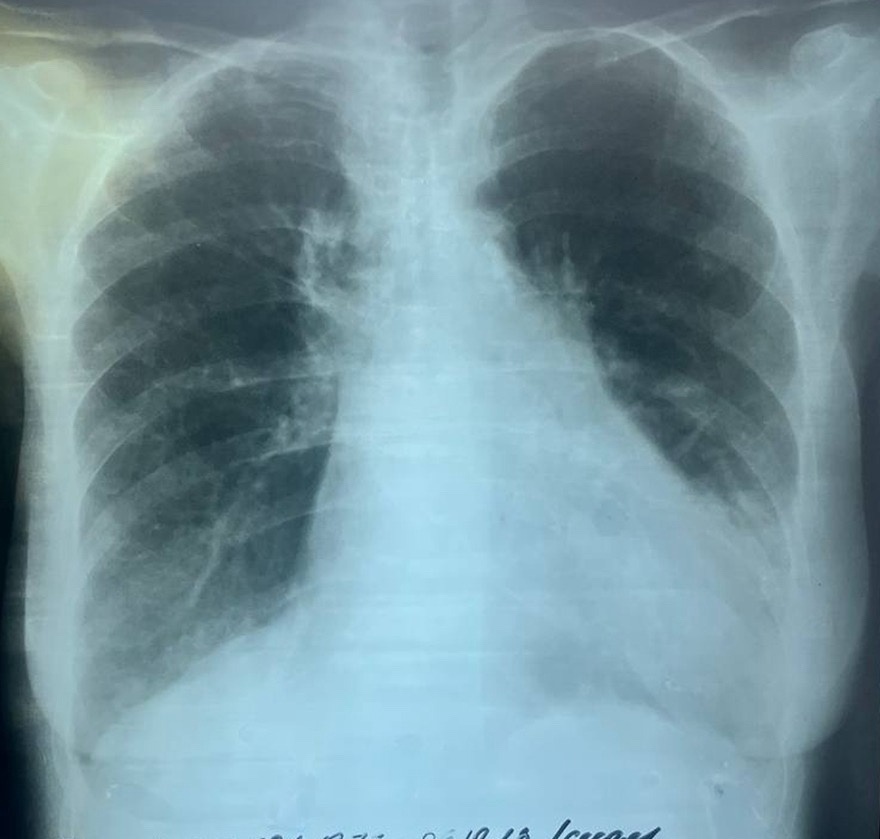

Острая внебольничная пневмония по МКБ-10: признаки и примеры